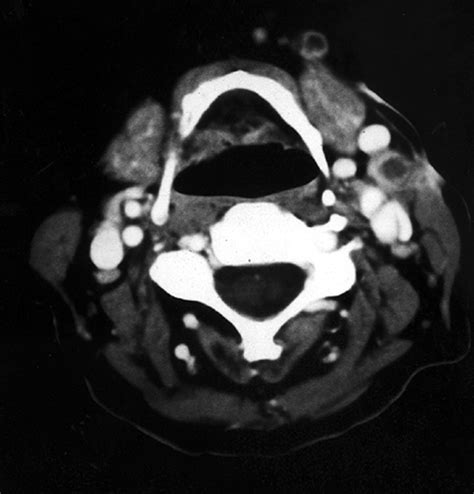

• Imaging Tests: Imaging tests, such as ultrasound, CT scan, or MRI, can help visualize the lymph nodes and detect any abnormalities.